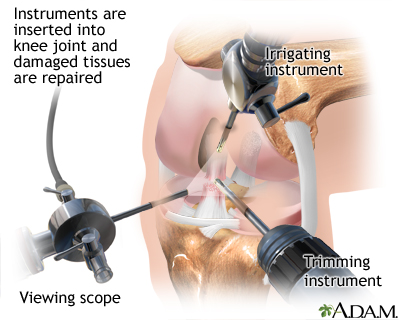

- Surgery to reconstruct the ACL

Knee arthroscopyACL reconstruction